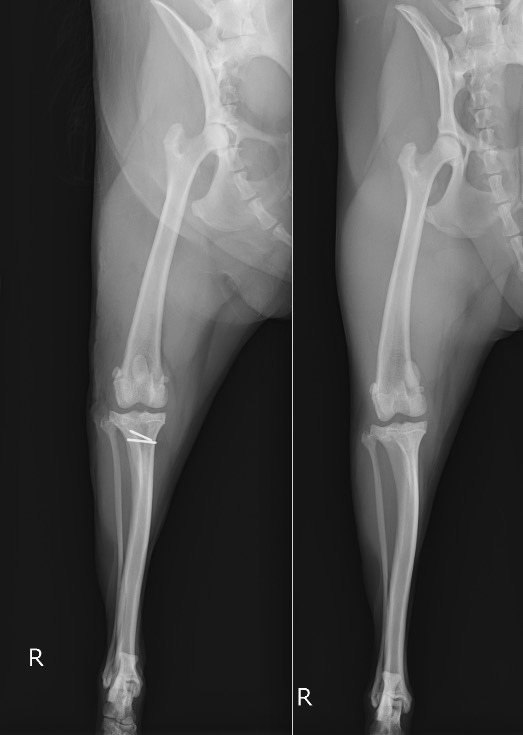

術前・術後のX線を見比べると、膝蓋骨が真ん中に整復されていることが分かります。

白く見えるのはステンレス製のピンであり、脛骨粗面転移という手技を行ったために使っています。

右後肢 【左:術後 / 右:術前】